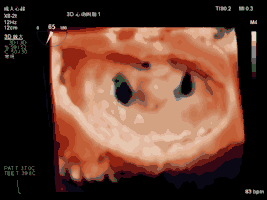

夹合术中(左房面观):三维心超示夹合后双孔征

夹合术中(左室面观):三维心超示夹合后双孔征